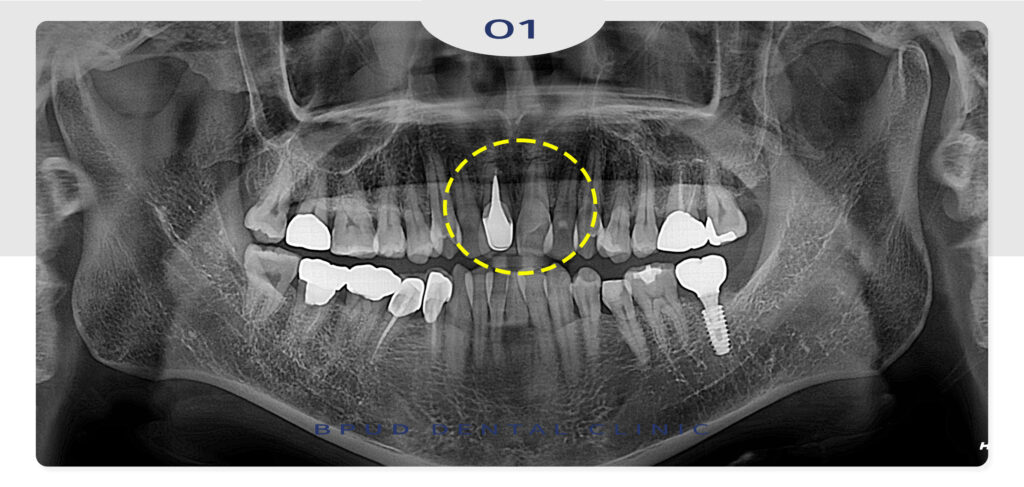

환자분께서는 오랫동안 콤플렉스였던

삐뚤빼뚤한 앞니의 부정교합과 덧니의 문제를

해결하고 싶으시다며 내원해 주셨는데요.

본원에서 왼쪽 아래 어금니 임플란트 식립을

진행해보셨던 환자분께서는 앞니의 심한 부정교합으로

단순히 치아 삭제 후 크라운 수복만으로

문제를 해결하기에는 어려움이 있었는데요.